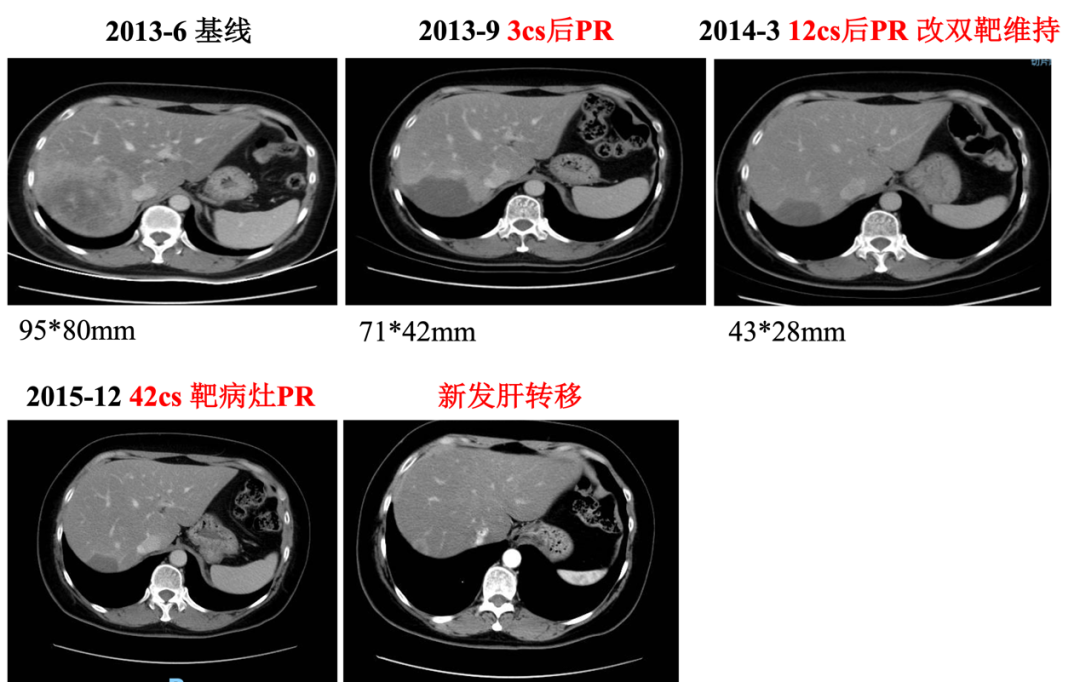

▌影像学检查:

2013年6月30日腹部CT:肝右后叶病灶并肝内多发子灶,考虑M,病灶总范围8.0*5.8cm,其病灶周围可见多发异常廓清子灶(4-5个),最大约1.6cm;

图1. 腹部CT

▌一线治疗:

入组MO28047临床试验(PERUSE研究),于2013-7-16开始行紫杉醇+曲妥珠单抗+帕妥珠单抗方案治疗,具体:紫杉醇175mg/m2 270mg d1;帕妥珠单抗首剂840mg,以后420mg d1;曲妥珠单抗首剂 8mg/kg 484mg,以后6mg/kg 363mg d1,Q21d。最佳疗效PR,自第10周期调整为双靶维持治疗。2015年12月(42周期时)原靶病灶维持PR,新发18mm肝转移,评效病情进展,PFS为30月。不良反应:腹泻2级,粒细胞下降2级。